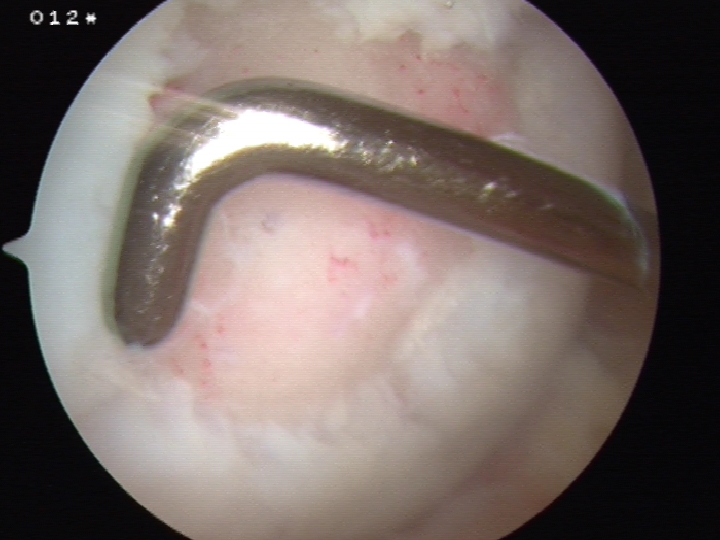

Technique

Debride all tissue from defect

- obtain osteochondral plugs 4.5 mm

- periphery of femoral trochlea / notch

- create cylindrical holes with drill

- insert osteochondral plug

- small gaps between plugs

- ensure slightly recessed